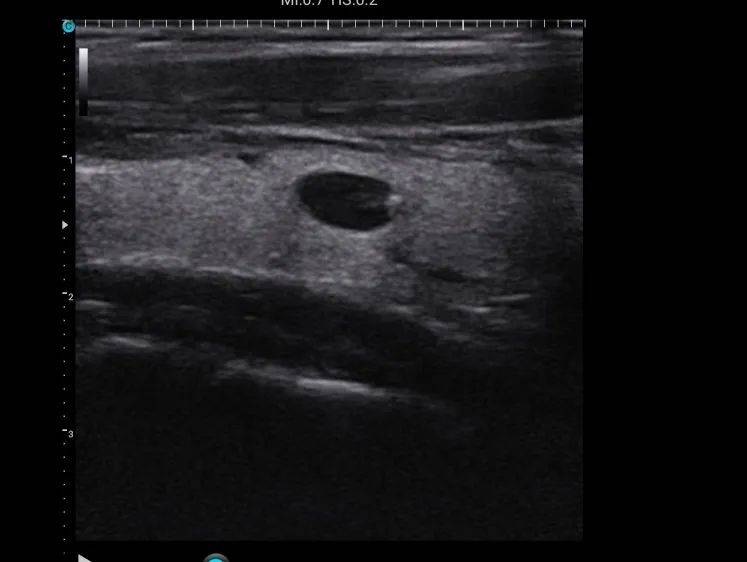

单发结节和多结节超声图像